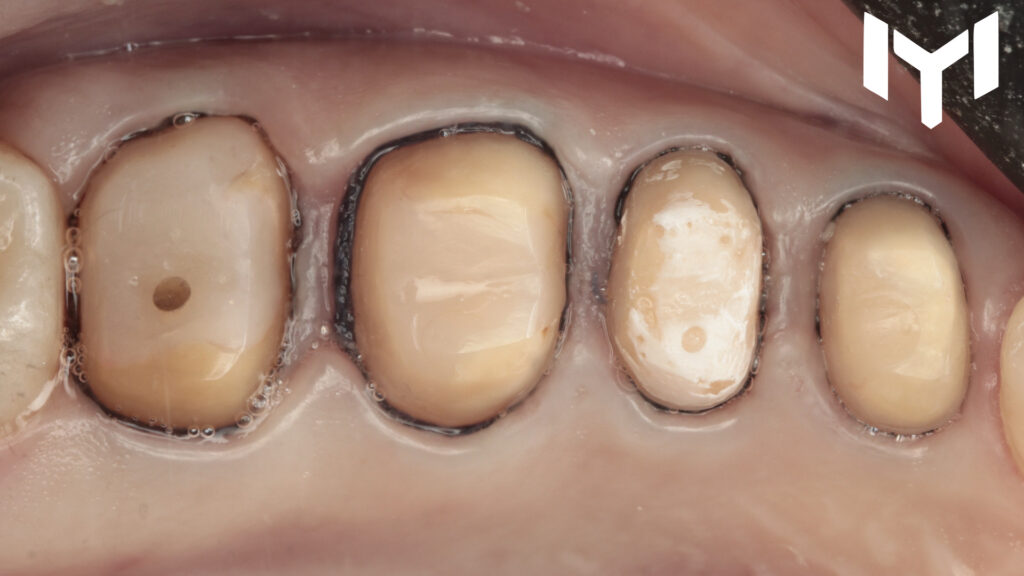

1- vertical preparation for the segment.

3. The Final Restoration: Zirconium after one month, the soft tissue showed remarkable health and stability. We transitioned to the final Zirconium crowns with highly finished and polished not glazed cervical collar.